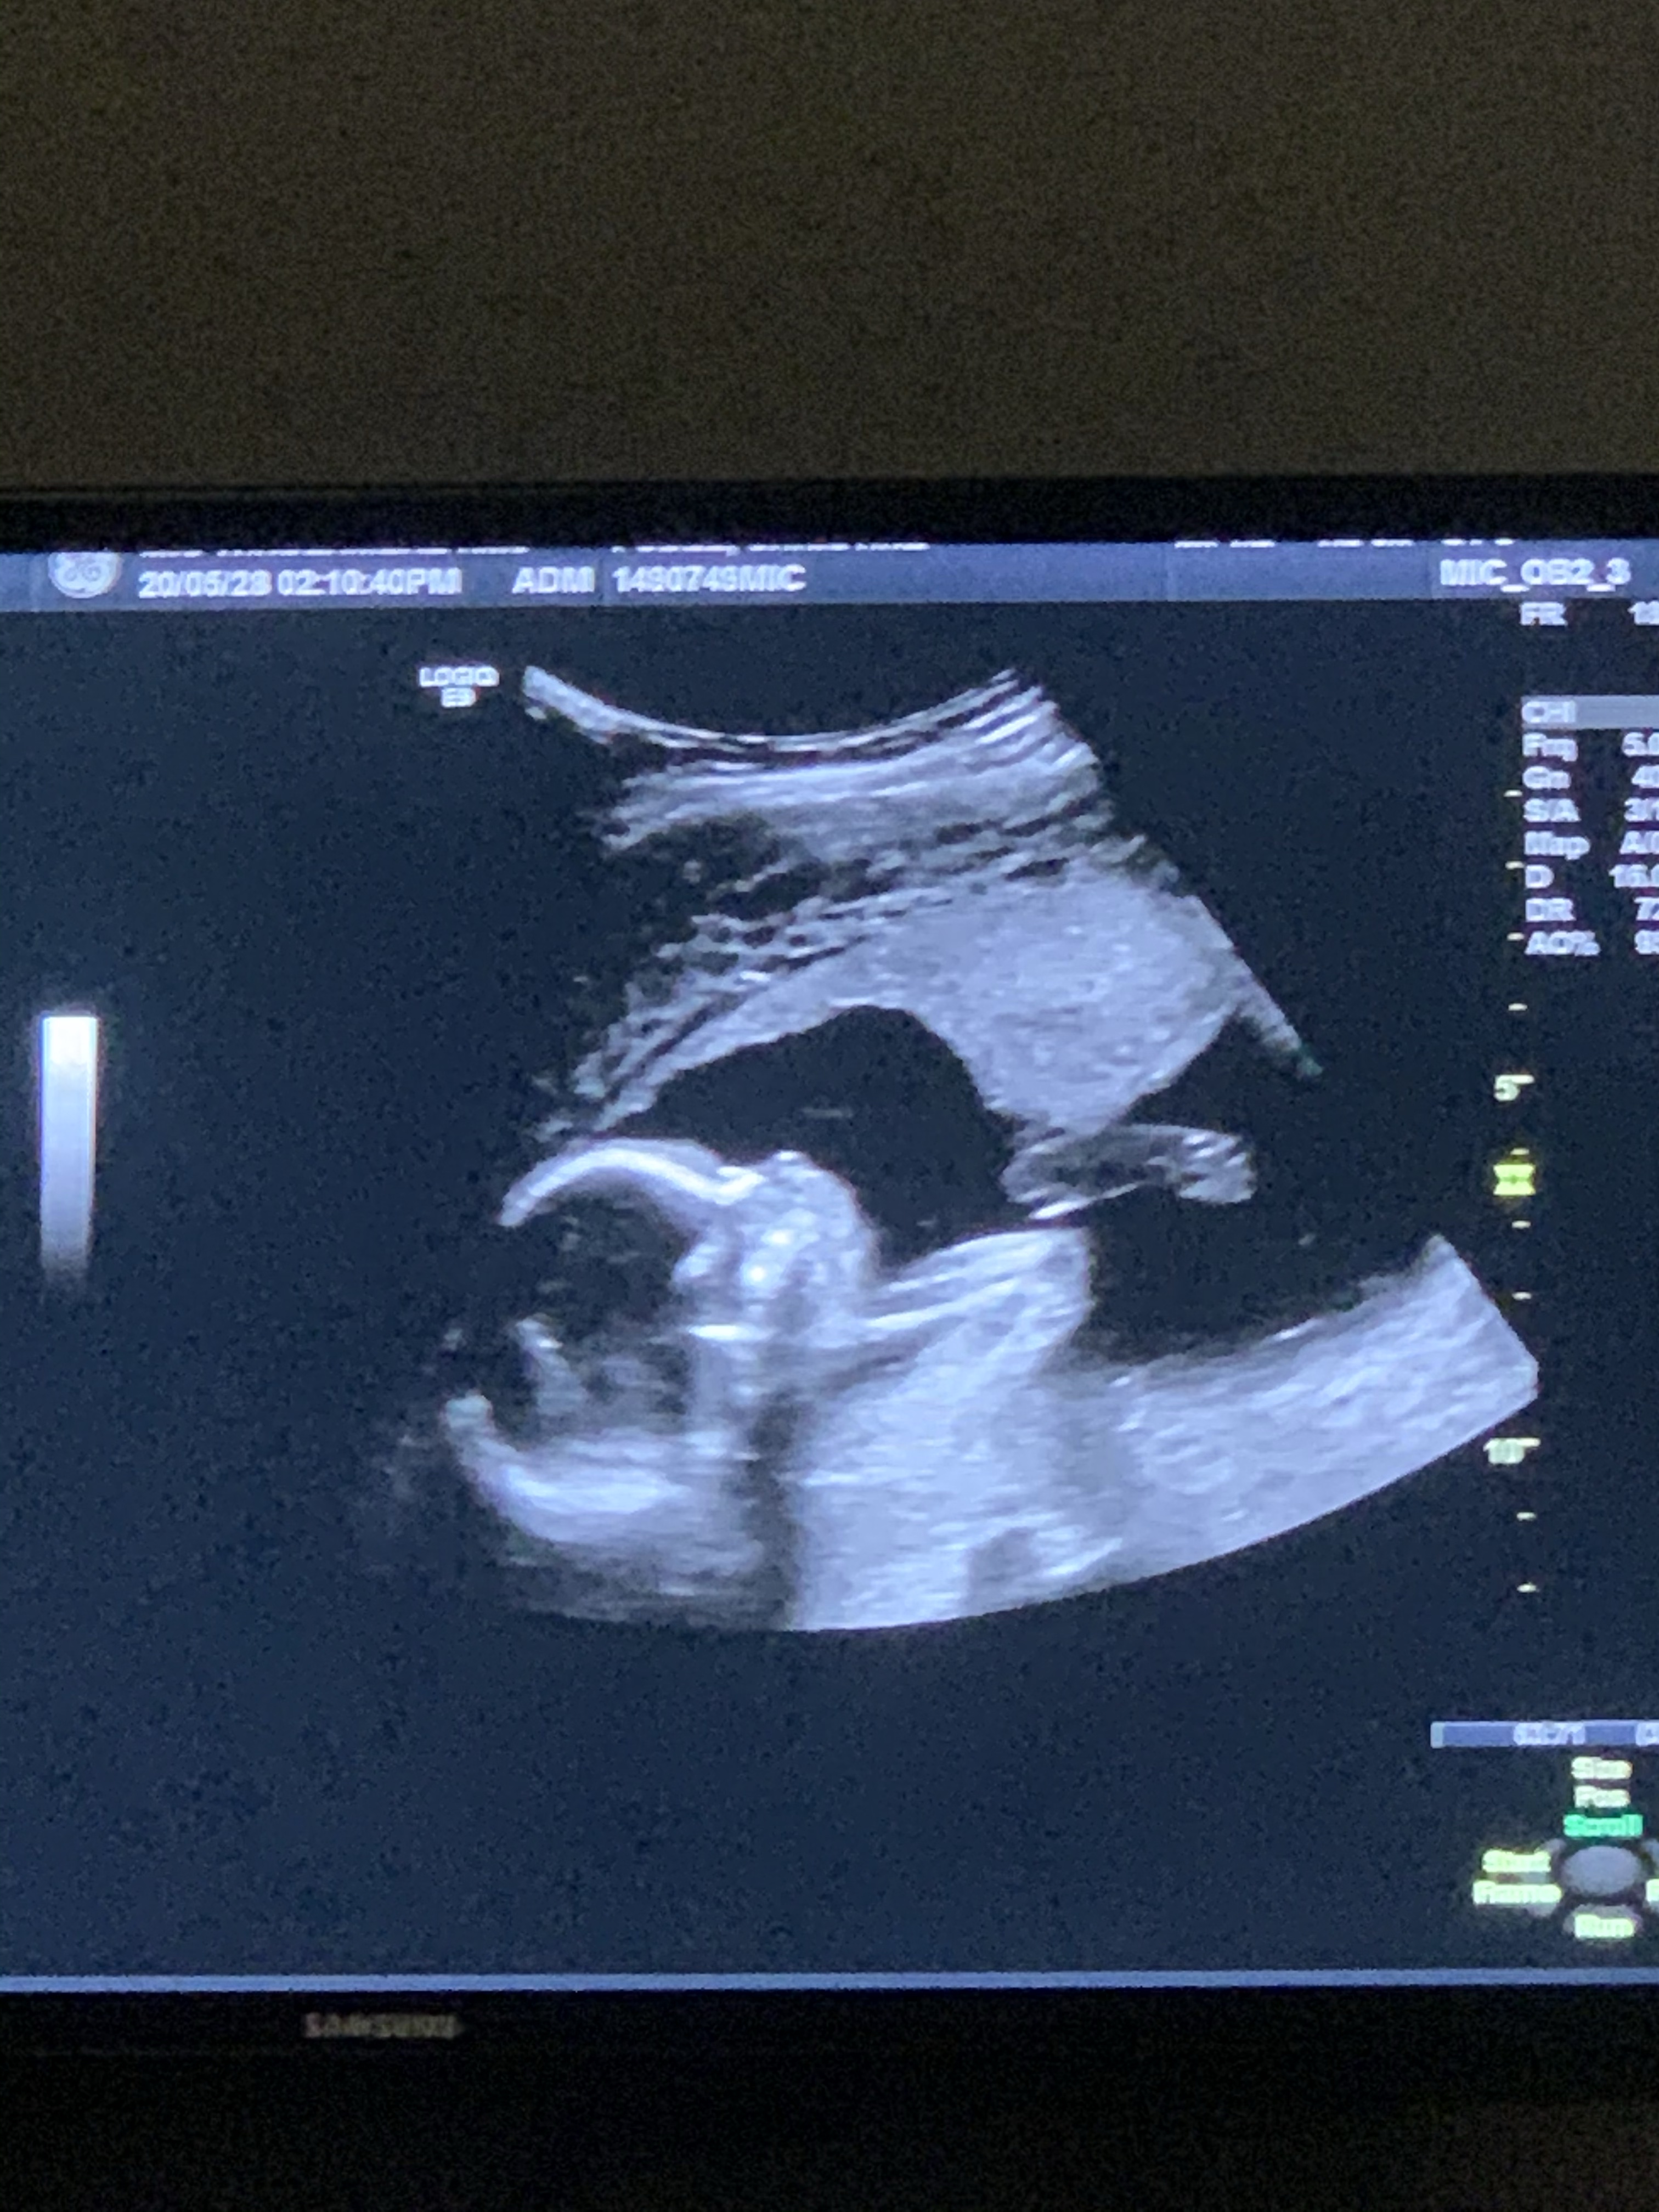

At 15 weeks, I had another bleed, this one probably the biggest one that I have had yet. I ended up in the hospital to get checked out, with blood work and another ultrasound.

Now we found a few more reasons why I could possibly be bleeding. First the subchorinic hematoma is still there, most likley still actibely bleeding. Plus my placenta is in the front and quite low, at least on the ultrasound done in the hospital which could be another reason.